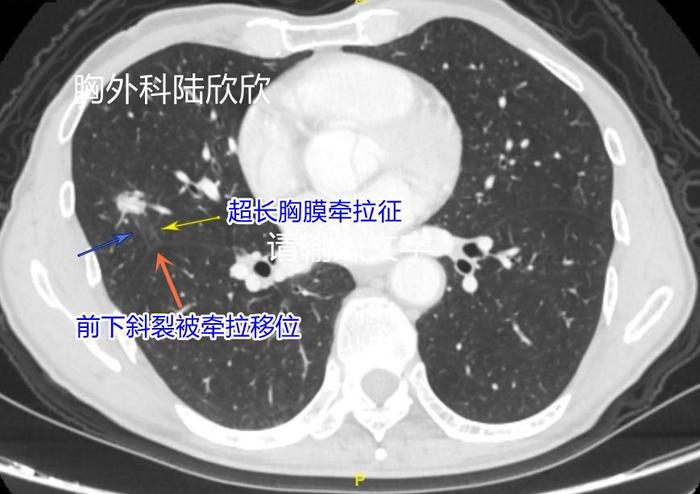

九、 长腿机器人形磨玻璃结节

超长的胸膜牵拉征像是机器人的两条腿。这个混合磨玻璃结节的病理是浸润性腺癌。